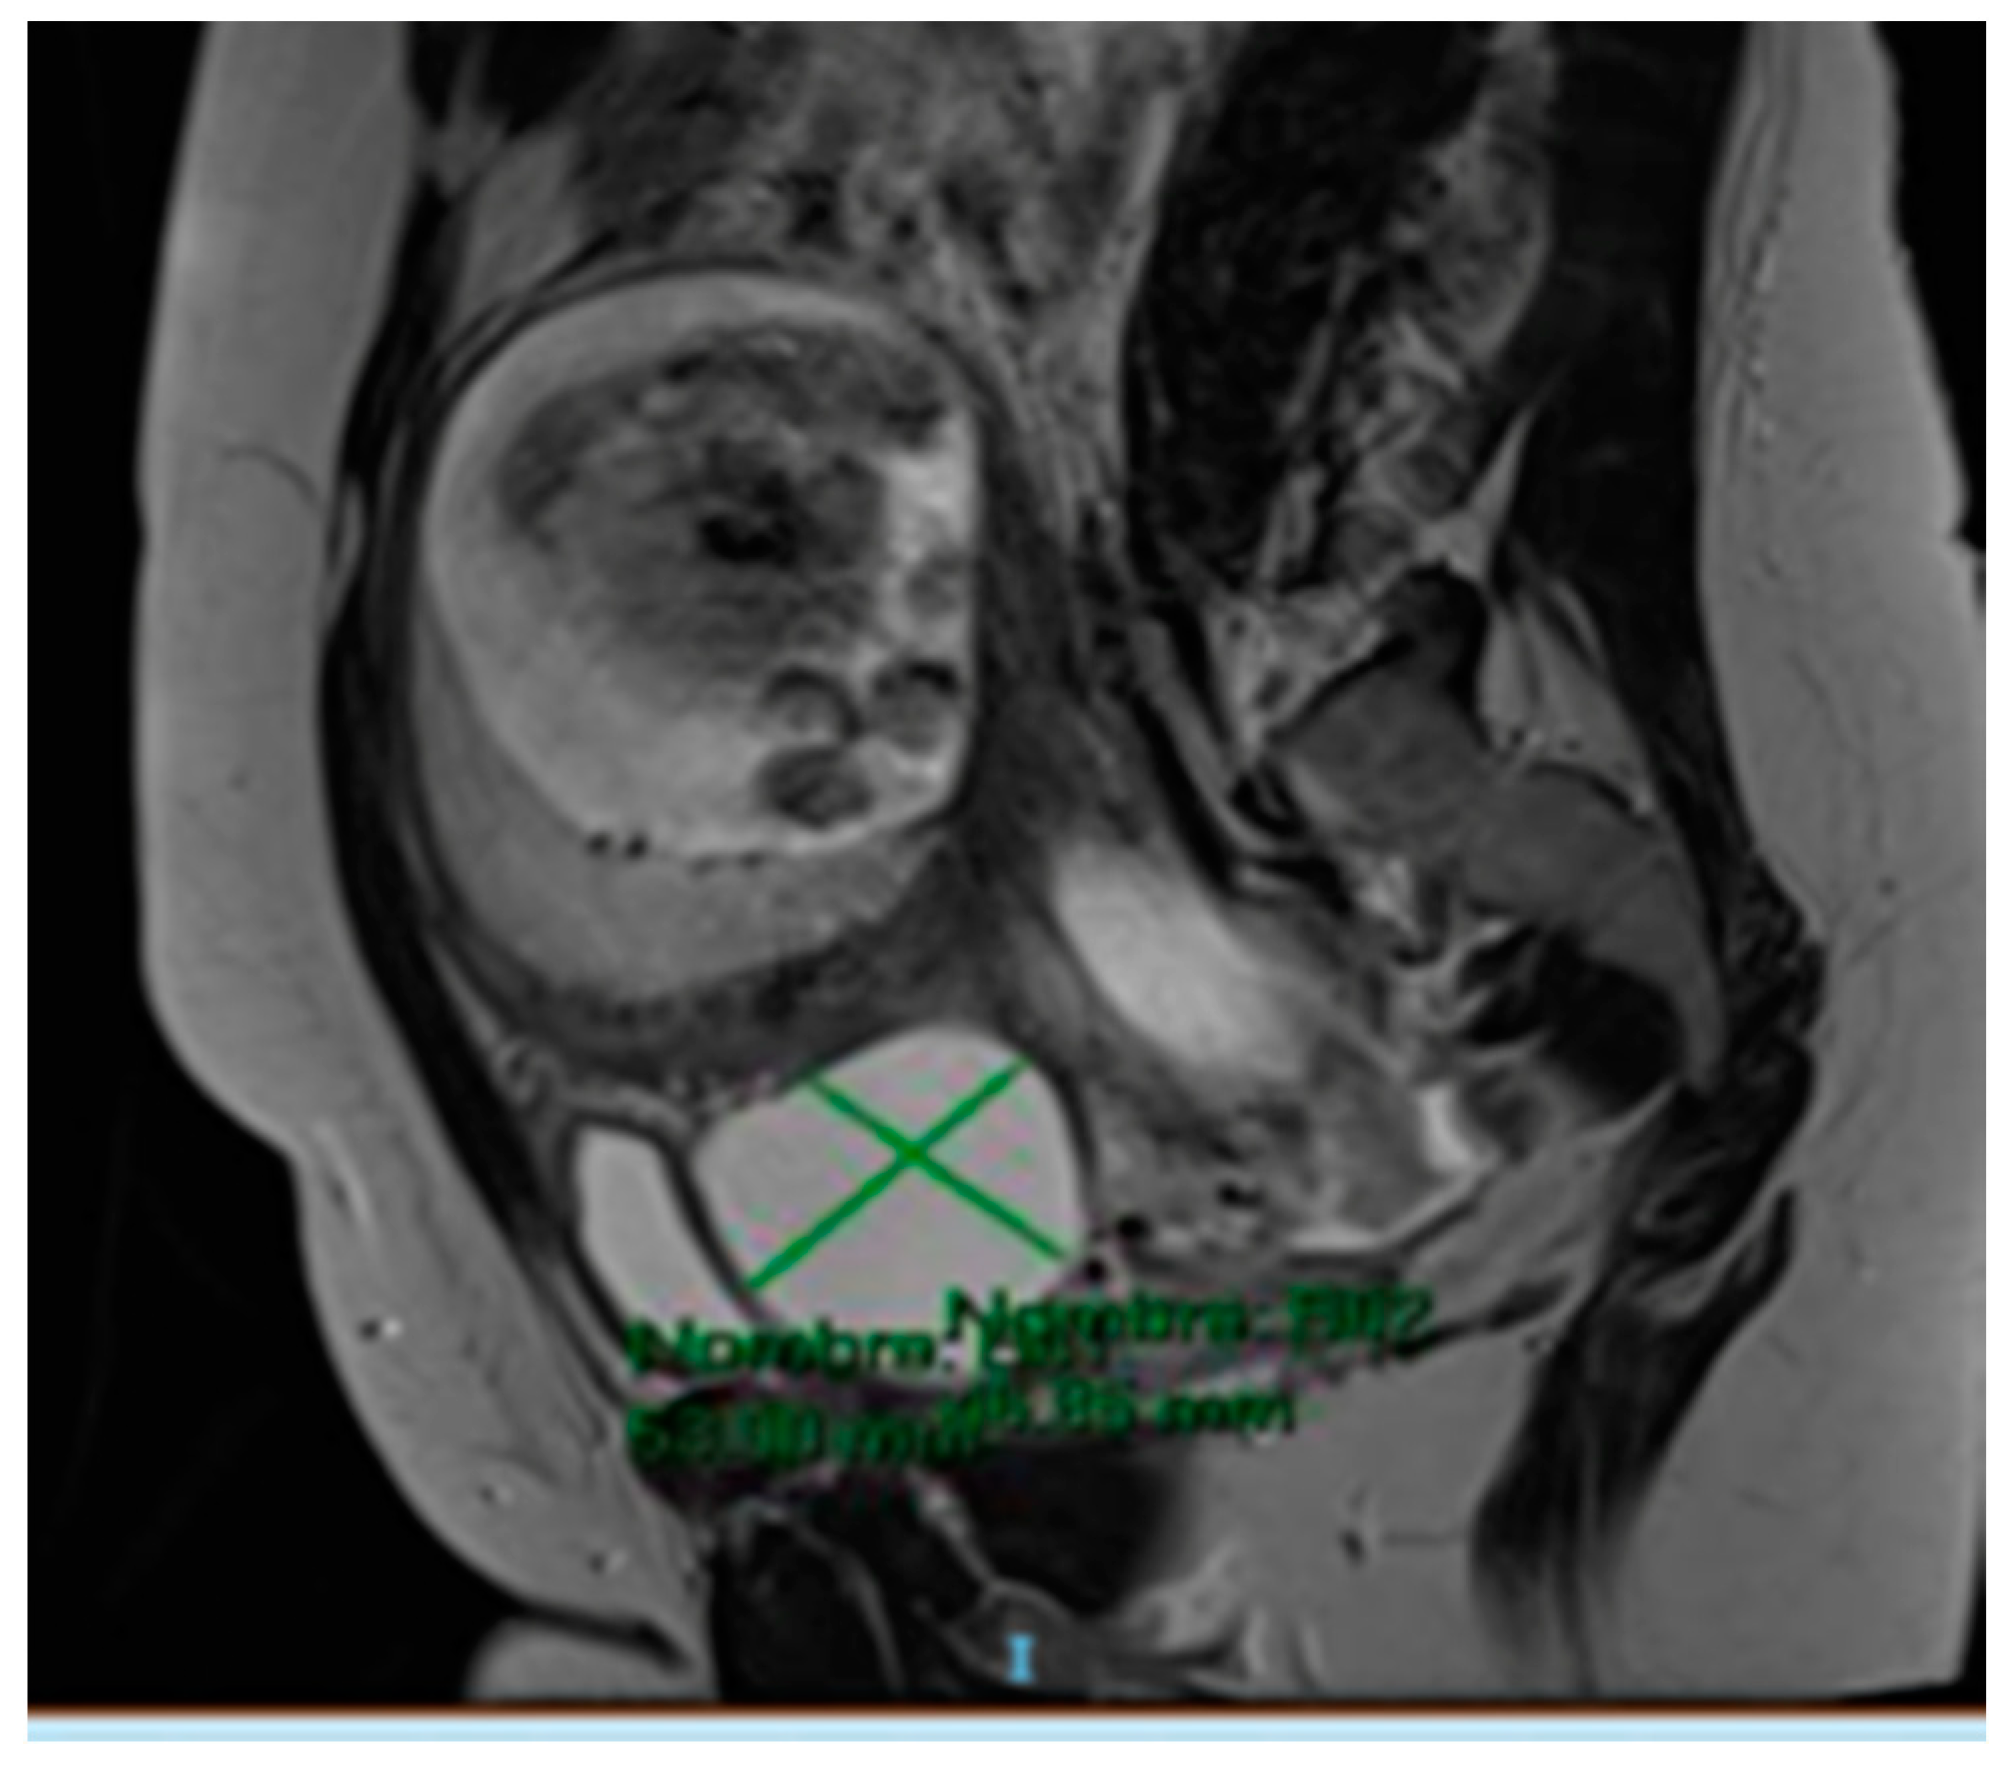

The MRI (Magnetic Resonance Imaging) scan showed 53 mm × 46 mm thin-walled cysts with a septum in the right paracervical area, another 27 mm × 20 mm cystic formation in the left hemipelvis (Figure 2 and Figure 3) and presacral 2 cm cysts containing a solid pole.

Figure 2.

MRI scan compatible with 27 mm × 20 mm cystic formation in the left hemipelvis.

Figure 3.

MRI scan compatible with 53 mm × 46 mm cystic formation in the right paracervical area.